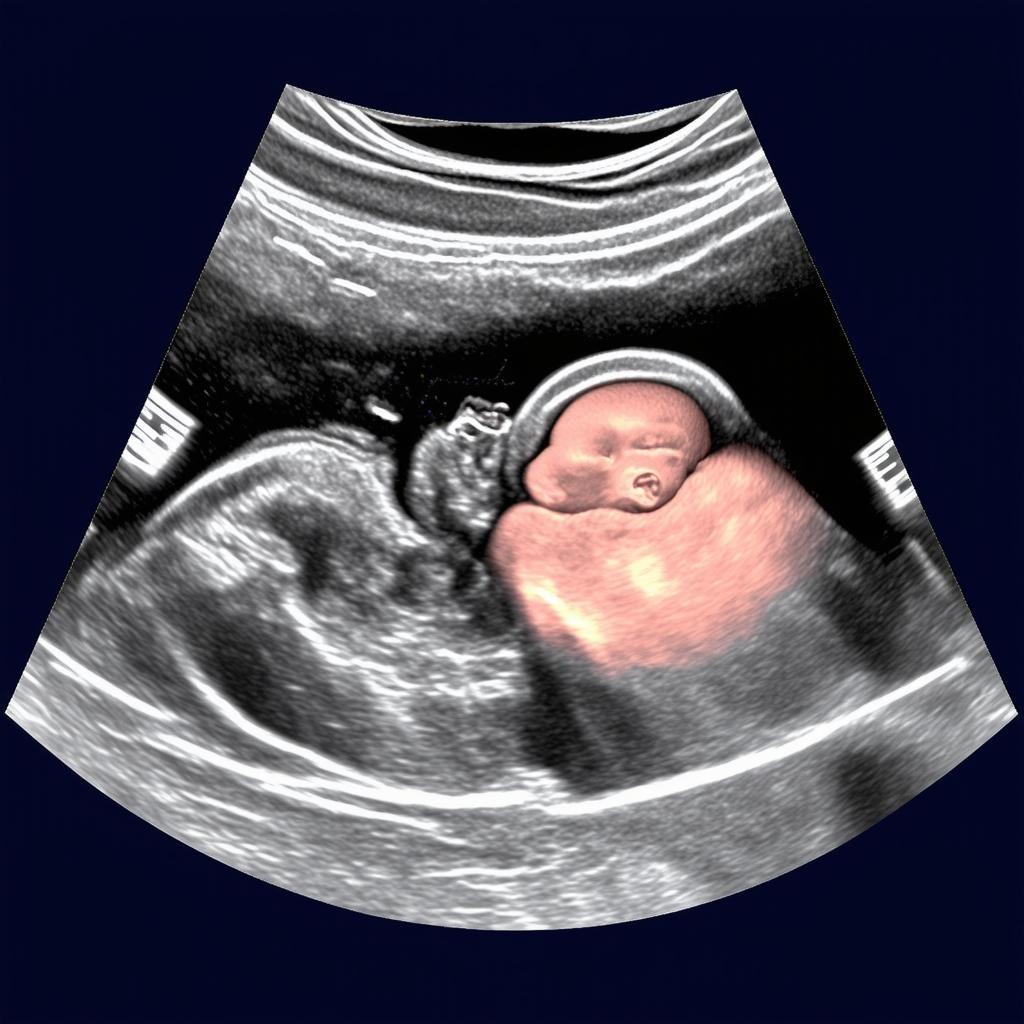

Показатели УЗИ на 20 неделе беременности: норма и анатомия плода

20 неделя беременности — это важный этап, когда проводится второе плановое ультразвуковое исследование (УЗИ). На этом сроке врач оценивает развитие плода, его анатомию, а также состояние плаценты и околоплодных вод. Это исследование помогает выявить возможные отклонения и убедиться, что беременность протекает нормально.

К 20 неделе беременности плод уже полностью сформирован, и врач может детально изучить его анатомию. Вот основные структуры, которые оцениваются во время УЗИ:

1. Головной мозг: проверяется структура полушарий, мозжечка и желудочков.

2. Сердце: оценивается частота сердцебиения (норма — 120-160 ударов в минуту) и строение камер.

3. Позвоночник: проверяется целостность и отсутствие деформаций.

4. Внутренние органы: почки, желудок, мочевой пузырь и кишечник должны быть хорошо видны.

5. Конечности: врач проверяет наличие всех пальцев на руках и ногах.